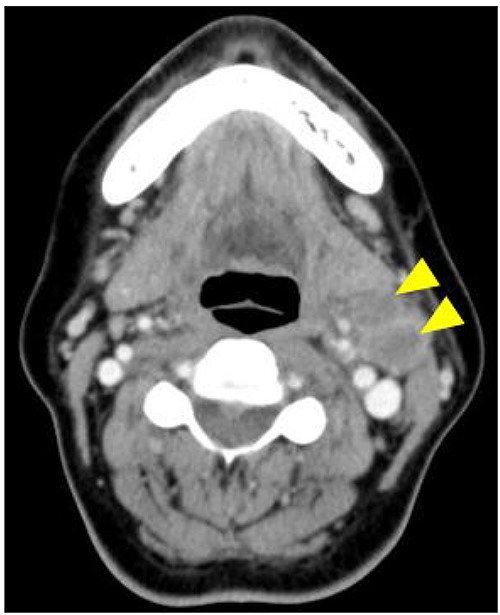

The postoperative course was uneventful; however, rapid enlargement of left cervical lymph nodes was observed at 1 month after surgery. Contrast-enhanced CT showed enlarged left cervical lymph nodes with ring enhancement, and a diagnosis of secondary cervical lymph node metastasis was made (Fig. 1). Left radical neck dissection was performed under general anesthesia in October 2014, and a thick thoracic duct was found in the supraclavicular fossa during surgery. There was no leakage of lymph after ligation and cutting of the thoracic duct (Fig. 2), and the operation was completed following placement of three suction drains in the left neck.

Contrast-enhanced CT is showing enlarged left cervical lymph nodes with ring enhancement (arrowheads).